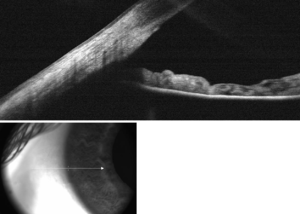

Enlarged general view of the iridial angle. (When enlarged, visible with older label of 'trabecular tissue') | |

الشبكة الحويجزية/التربيقية (Trabecular Meshwork) هي منطقة من الأنسجة في العين تقع حول قاعدة القرنية ، بالقرب من الجسم الهدبي ، وهي مسؤولة عن تصريف الخلط المائي من العين عبر الغرفة الأمامية (الغرفة الموجودة في مقدمة العين المغطاة القرنية).

تنقسم الشبكة إلى ثلاثة أجزاء، مع بنى تحتية مختلفة مميزة:

- الشبكة العنبية الداخلية (Inner uveal meshwork): الأقرب إلى زاوية الغرفة الأمامية ، تحتوي على ترابيق رفيعة تشبه الحبل ، موجهة في الغالب بطريقة شعاعية ، وتحيط الترابيق بمساحات أكبر من الشبكة الشبكية القرنية.

- شبكة القرنية والصلبة (Corneosclearal Meshwork) - تحتوي على كمية كبيرة من الإيلاستين ، مرتبة كسلسلة من الصفائح الرقيقة ، المسطحة ، المثقبة مرتبة في نمط رقائقي ؛ يعتبر وتر العضلة الهدبية.[2]

- النسيج المجاور للقناة (Juxtacanalicular tissue، ويُعرَف أيضًا باسم النسيج الشبكي المصفى) - يقع مباشرة بجوار قناة شليم Schlemm's canal، ويتكون من مادة قاعدية من النسيج الضام مليئة بالجليكوامينوجليكان والبروتينات السكرية. هذا الشريط الرفيع من الأنسجة مغطى بطبقة أحادية من الخلايا البطانية.